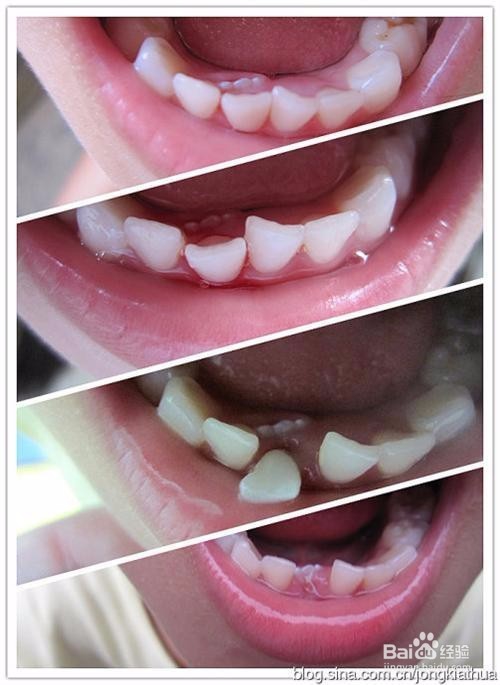

1、乳牙滞留。随着生活水平的提高,食物的日益精细化,孩子对乳牙的磨耗降低,很容易导致乳牙滞留,这些滞留的乳牙必须要拔除,否则可能会给恒牙的萌出造成影响,比如会导致萌出的恒牙出现歪斜,造成牙齿畸形。